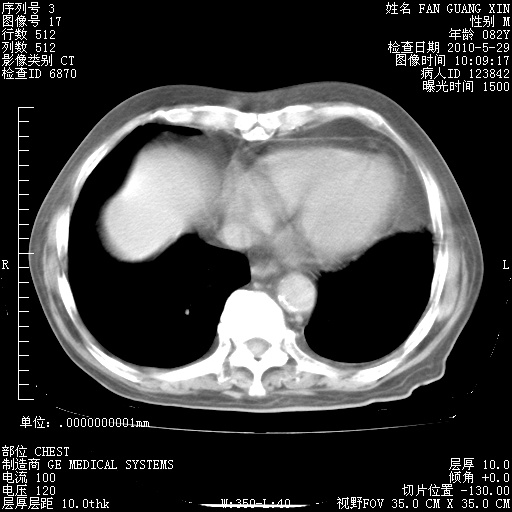

再治疗10天后的肺部CT

再治疗10天后的肺部CT 纵膈窗

阅读此次胸部CT,肺间质渗出性改变较入院时有吸收。目前从体温、白细胞、中性分叶明显增高,肯定存在细菌感染(发生医院感染哦,若无消化道及泌尿系统等感染的依据,肺部感染可能大)。若你院头孢哌酮舒巴坦钠耐药率较高,同意你的方案,若48小时体温仍高,可考虑使用碳青霉稀类抗菌药物,同时可予超声雾化、注意滴数时加大液体量。白蛋白33.30g/L较低哦,需加强营养等支持治疗。